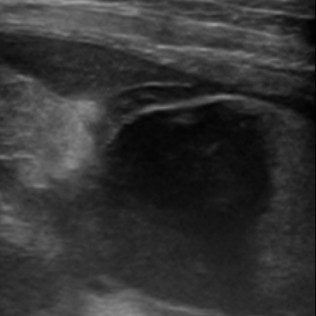

→ OO이의 영상 진단(초음파)에서 담낭 파열이 확인되어

이후 신속한 담낭제거술을 진행했습니다.

복부 초음파: 담낭벽의 파열, 담즙의 복강 내 누출 확인